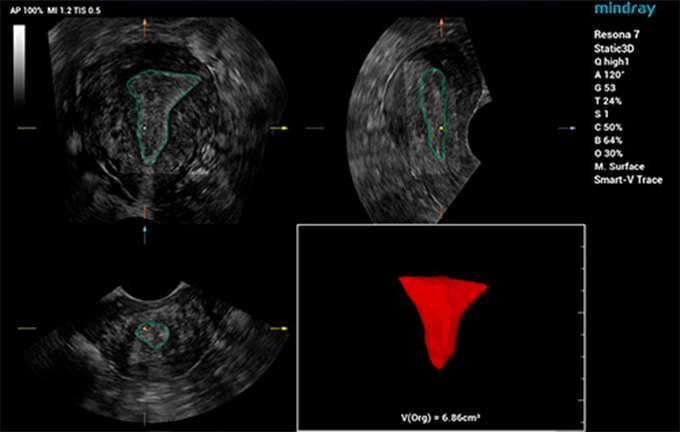

Mindray, sonografi uzmanlar?n?n karma??k pelvik taban muayenelerinde standartla?t?r?lm?? kesitleri ve ?l?Þmleri h?zl?ca elde etmesine ve te?his verimlili?ini art?rmas?na yard?mc? olmak i?in, ak?ll? bir taban ultrason ??zÞmÞ olan Smart Pelvic'i geli?tirdi. Tam pelvik ?l?Þmleri otomatik olarak yapabilir ve levator hiatusun otomatik 3B g?rÞntÞlemesiyle birlikte, uzunlamas?na ?ap, enine ?ap, levator hiatus alan? ve levator Þretra bo?lu?unun boyut ?l?Þmlerini sunar. Sonografi uzmanlar?, birka? basit etkile?imde do?ru de?erlendirme yapmak i?in kapsaml? klinik veriler elde edebilir, geleneksel muayenelerin yaln?zca 1/3âÞ kadar sÞre kullan?l?r. Ayr?ca Mindray, farkl? prob tÞrlerini ve standartla?t?r?lm?? ?al??may? destekleyen Þ? temel endÞstriyel standart sunar.

Smart Pelvic